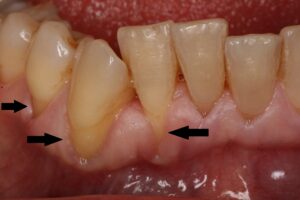

Rezessionen/freiliegende Zahnhälse – Die erste Abbildung zeigt freiliegende Zahnhälse (schwarze Pfeile), die als ästhetisch störend empfunden werden können. Bei entzündungsfreiem Zahnfleisch können durch eine Zahnfleischverpflanzung die freiliegenden Zahnhälse wieder gedeckt werden. Auf der zweiten Abbildung ist der gleiche Patient drei Monate nach Zahnfleischverpflanzung zu sehen. Die Zahnhälse sind wieder vollständig gedeckt.

Durch derartige Zahnfleischdefekte entstehen lange freiliegende Zahnwurzeln, die zu einer Empfindlichkeit auf Hitze, Kälte oder stark süße beziehungsweise saure Speisen führen können. Ferner können diese freiliegenden Zahnwurzeln für Patienten ein ästhetisches Problem darstellen, insbesondere, wenn diese im Frontzahnbereich auftreten und beim Lachen sichtbar werden. Aus medizinischer Sicht ist neben der Überempfindlichkeit der betroffenen Zähne vor allem eine erhöhte Gefahr einer Wurzelkaries relevant. Ursachen hierfür sind die geringere Widerstandsfähigkeit der Zahnhartsubstanzen der Wurzel gegen die Säuren der Kariesbakterien und die größere Rauigkeit der Wurzeloberfläche, die eine bakterielle Besiedlung begünstigt. Die Bakterien können wiederum eine Entzündung des Zahnhalteapparates auslösen, was eine vorhandene Parodontitis verstärken und einen Teufelskreis mit einer Verschlechterung der lokalen Entzündung auslösen kann. Dies führt zu einem voranschreitenden Knochenabbau, der zur Lockerung des Zahnes und letztendlich zum Verlust desselben führen kann.